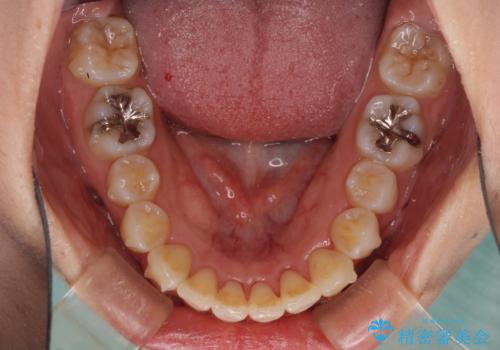

歯列全体の拡大と、歯と歯の間を削ることでスペースを獲得し、インビザラインによる矯正治療を行うこととしました。

骨格的な問題を抱えた左奥以外は比較的早く咬み合わせが改善しましたが、左奥はどこで咬み合えば良いのか分からず、大変不便な思いをされていました。

ゴムかけにご協力いただき、最終的には反対咬合を改善することができ、患者様には大変満足していただきました。